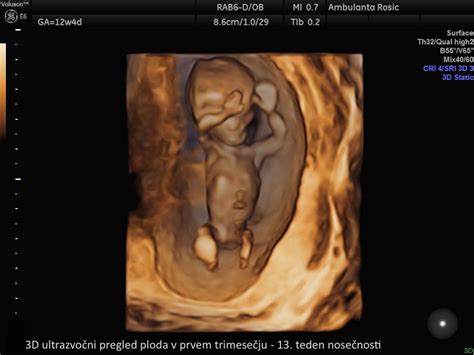

- Ultrazvočni pregled: V tretjem trimesečju ultrazvok omogoča spremljanje rasti ploda, oceno njegovega stanja (z merjenjem pretokov, količino plodovnice in zrelostjo posteljice) ter preverjanje lege ploda.